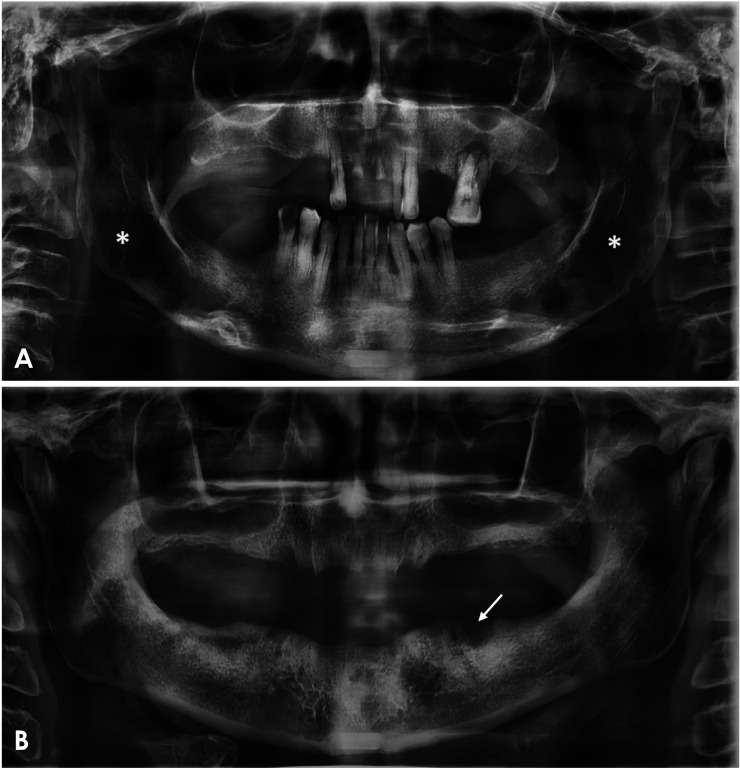

Results: Six studies, involving 669 MM patients, were included, with 447 receiving bisphosphonate treatment. The majority were treated with pamidronate, zoledronate, or a combination of both. Seventy patients developed medication-related osteonecrosis of the jaw (MRONJ), predominantly in the mandible, characterized by the presence of bony sequestrum, bone sclerosis, increased periodontal ligament space, osteolytic lesions, and osteomyelitis as observed in imaging analyses. For non-MRONJ lesions, the mandible also exhibited the highest frequency of asymptomatic bone alterations. These ranged from "punched-out" osteolytic lesions or "soap bubble" lesions to solitary bone lesions, areas of bone sclerosis, abnormalities of the hard palate, osteoporosis, non-healed alveoli, and cortical bone rupture.

Conclusion: MM patients treated with bisphosphonates display radiographic patterns of maxillomandibular bone lesions. These patterns aid in diagnosis and facilitate early and targeted treatment, thereby contributing to improved morbidity outcomes for these patients.